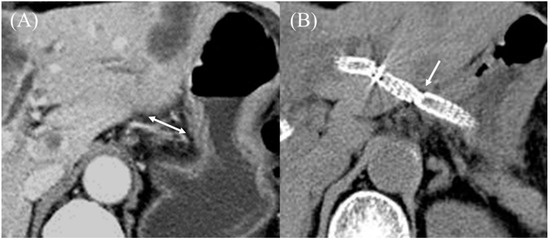

- Yamamoto, Y.; Ogura, T.; Nishioka, N.; Yamada, T.; Yamada, M.; Ueno, S.; Higuchi, K. Risk factors for adverse events associated with bile leak during EUS-guided hepaticogastrostomy. Endosc. Ultrasound 2020, 9, 110–115. [Google Scholar] [CrossRef]

- Ishiwatari, H.; Satoh, T.; Sato, J.; Kaneko, J.; Matsubayashi, H.; Yabuuchi, Y.; Kishida, Y.; Yoshida, M.; Ito, S.; Kawata, N.; et al. Bile aspiration during EUS-guided hepaticogastrostomy is associated with lower risk of postprocedural adverse events: A retrospective single-center study. Surg. Endosc. 2021, 35, 6836–6845. [Google Scholar] [CrossRef]